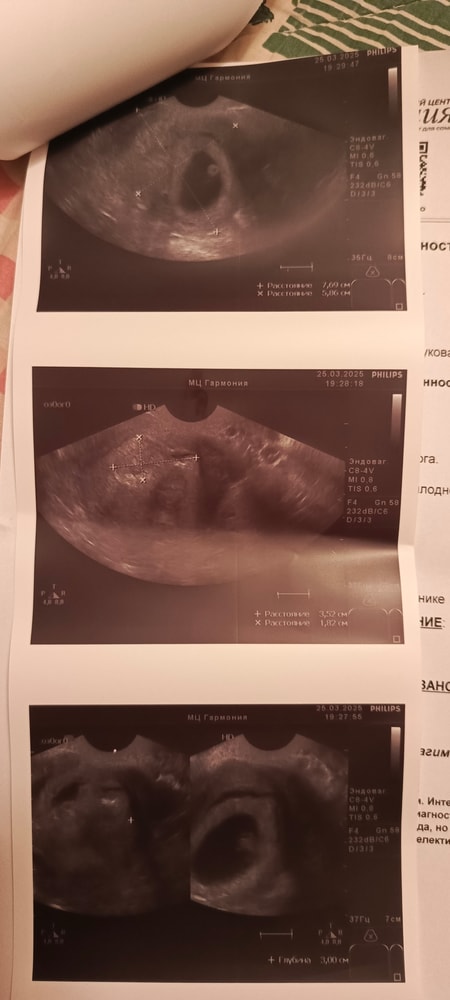

Вторая полость в матке. Двурогая матка?

Ну, вижу перегородку тоже Попробуйте переделать УЗИ у еще специалиста, моей маме сказали про двурогость когда она забеременела только младшей сестрой моей, а у меня еще старшая и я)) у меня двурогость, обратили сразу при первом обследовании

Lisa, не переживайте, снимки не четкие, одна полость, одно плодное яйцо. Перегородка она при двурогой матке есть У вас нет, сравнила свои снимки, у вас не так

Alenchik, прикрепила в исходное сообщение фото узи

Наше узи Размер плода 16+5